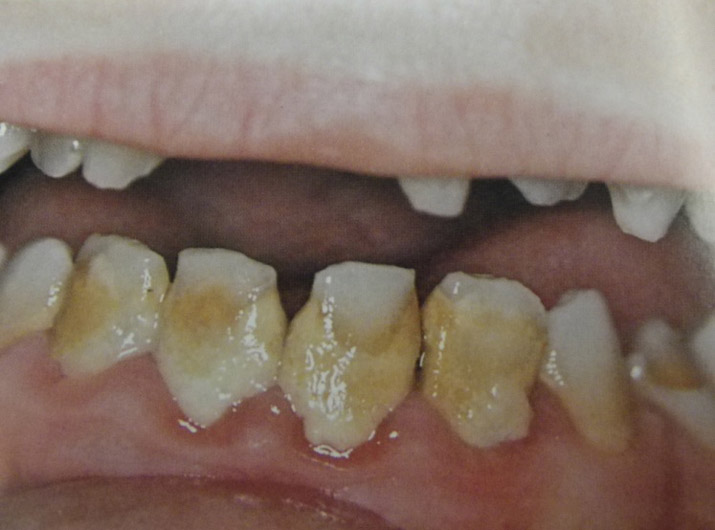

Υπενασβετίωση της αδαμαντίνης

Συνήθως εκδηλώνεται με λευκές, κίτρινες ή καφέ κηλίδες στους τομείς και τους γομφίους, μπορεί όμως να επηρεάσει και άλλα δόντια. Η κλινική εικόνα μπορεί να περιορίζεται μόνο στην εμφάνιση αυτών των κηλίδων, ή να είναι πιο σοβαρή προκαλώντας απώλεια της αδαμαντίνης του δοντιού, με συνέπεια την εμφάνιση ευαισθησίας και πόνου καθώς και τερηδόνας.

Η κατάσταση αυτή της αδαμαντίνης οφείλεται σε διαταραχή της διάπλασής της με αποτέλεσμα την ελλιπή ενσωμάτωση των μετάλλων στη δομή της. Έχουν ενοχοποιηθεί διάφοροι παράγοντες (περιβαλλοντικοί, ασθένειες της μητέρας και του βρέφους, διατροφή κ.ά.) οι οποίοι μπορούν να προκαλέσουν αυτές τις διαταραχές.